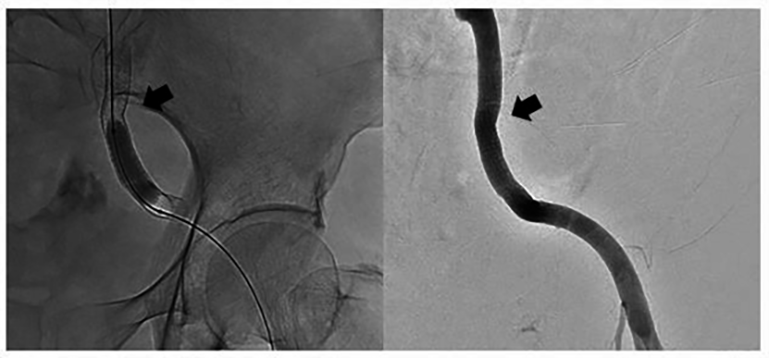

Fig. 3.A covered stent was introduced using a guide wire. Distal angiography showed no contrast agent overflow (between arrows).

Fig. 4.Angiography showed a small source of bleeding in the upper segment of external iliac artery stent (arrow).

Fig. 5.The second covered stent was placed and partial overlap the front one (arrow).

Emergency vascular interventional surgery was promptly performed while haemostasis and treatment of shock was administered simultaneously. The covered stent was placed rapidly in the ruptured external iliac artery pseudoaneursm to block the bleeding source and it also ensured blood supply to the lower limbs. However, it should be noted that she needed to undergo a second interventional surgery 5 hours later. This could have been related to leakage of the covered stent or increased blood pressure and vasodilation. Moreover, clinicians should be alert to complications such as stent obstruction, deformation and kinking, stent loss, intimal hyperplasia and infection after placement [24]. However, no such complications were observed in the patient during follow-up.